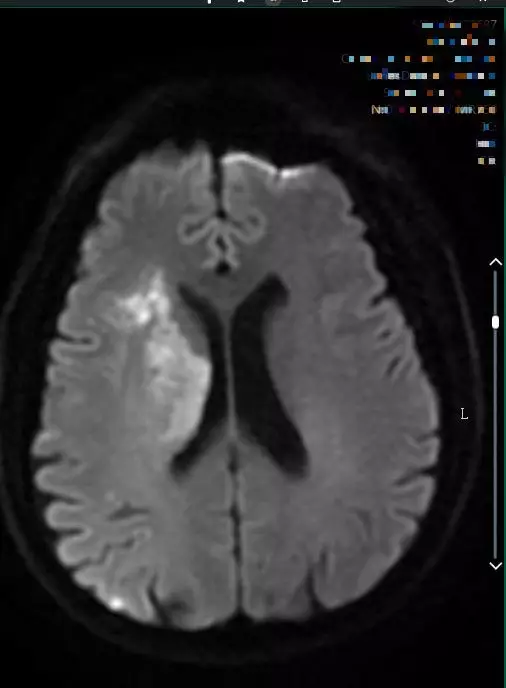

9:40分左右,患者逐渐开始出现烦躁、嗜睡,查体:言语不清,左侧肢体肌力0-1级,急查头颅MRI+MRA+颈部MRA阅片见,右侧基底节区急性脑梗死,右侧大脑中动脉闭塞。

头颅MRI+MRA(08-03日 11:50左右)

头颅MRI+MRA(2018-01-30日)